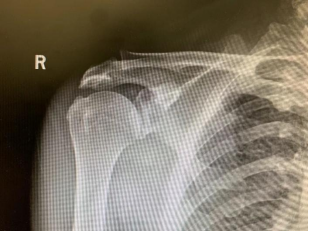

肩关节正位 关节骨赘

除了骨科医生查体,还可以通过一次简单的X线检查,即可提前判断您是否为先天性的III型肩峰,或肩峰下骨赘形成,判断您的肩关节是否适合羽毛球运动。

与其他检查手段比,X线检查的优点为直观、低成本、快速。肩关节X线检查首选肩关节正位、Y位,能清晰的显示肩峰形状和冈上肌出口位的形态。肩峰下骨赘形成,是肩峰下间隙狭窄的重要原因。间隙底部为肱骨头,顶部为喙突、肩峰以及连接两者的喙肩穹。由于这种结构关系,当有骨赘及III型肩峰存在,当运动者做上臂后伸,也就是上肢外展这个动作时,它就对肩袖组织造成一次撞击,从而产生肩袖损伤。

X线检查可表现为肩峰前缘硬化,肩峰下表面骨刺形成,肱骨大结节硬化或骨赘形成。如果X线片发现问题,可以再进行CT或者核磁共振(MRI)检查。CT扫描三维重建,显示肩关节结构更为清楚、直观,可观察X线片不易发现的关节内骨。核磁共振(MRI)对软组织分别率高,可显示肩袖病变。